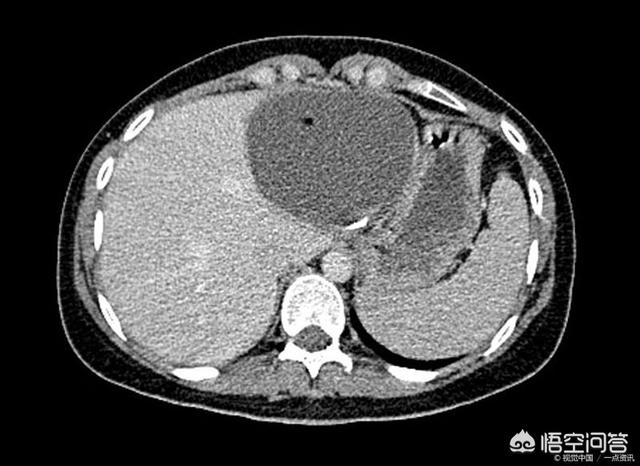

このタイプの肝嚢胞は良性病変であり、通常は明らかな臨床症状がなく、超音波検査やCT検査で偶然発見されるだけである。また、患者に腹痛や腹部不快感を引き起こす一部の大きな嚢胞だけが、通常女性に多い。

多発性肝嚢胞の肝機能の検査は一般的に正常であり、肝臓領域の超音波検査では、1つ以上の液体の安全性を見ることができます。 CTまたは核スキャンはまた、多発性肝嚢胞があるかどうかをチェックすることができ、さらに多発性肝嚢胞は実質的な病変がないことを決定することができます。